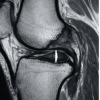

VAS scores showed progressive improvement post-operatively. The mean score decreased from 4 pre-operatively to 3.3 at 6 weeks, 2.2 at 3 months, and 0.8 at 6 months. By final follow-up, 92.9% of patients reported minimal or no pain (VAS 0–1), with no patient scoring ≥3 (image 2). A paired t-test comparing pre-operative and 6-month follow-up VAS scores demonstrated a statistically significant reduction in pain levels (t = 25.24, P = 0.00000000000198/P < 1.98 × 10⁻12), indicating that the improvement in VAS scores was highly significant. (Table 6)

Table 6: VAS score